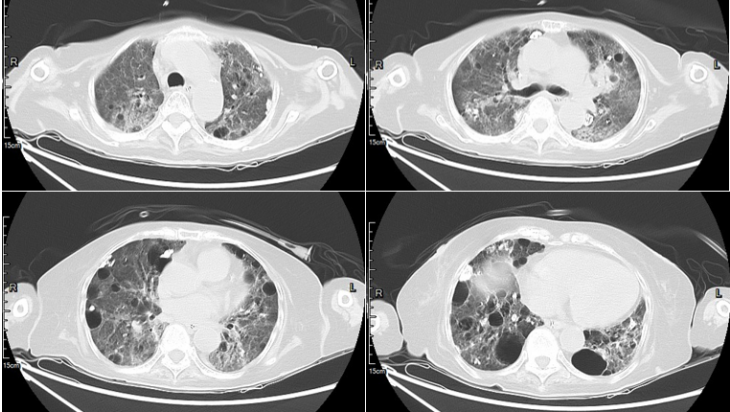

患者5月30日与6月26日胸部CT可以发现两肺磨玻璃渗出及肺气囊改变依然存在(图10,图11),这也提示后续康复可能要经历较长时间。患者之后转呼吸科普通病房继续康复训练,糖皮质激素逐渐减量,后出院转养老院。

图片

图10  患者胸部CT(2023-05-30)

图11  患者胸部CT(2023-06-26)